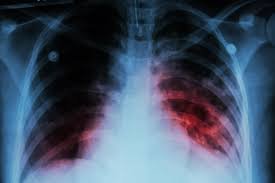

Durante el 2025 se notificaron en la provincia 884 casos de tuberculosis, lo que representa una baja del 8,6% en comparación con 2024, cuando se habían registrado 967 casos. En 2023, el número de notificaciones fue de 945.

Del total de casos confirmados, 43 corresponden a menores de 19 años y 12 presentaron algún tipo de resistencia a los medicamentos. La tuberculosis multirresistente se define como una forma de la enfermedad en la que los fármacos más potentes no resultan eficaces, situación que suele asociarse al abandono del tratamiento o a su incumplimiento según la indicación médica.

El tratamiento se hace con medicación antibiótica, que se debe seguir sin alteración por un mínimo de seis meses ya que, si el paciente abandona el tratamiento, o no lo cumple en forma rigurosa, puede desarrollar tuberculosis resistente a los fármacos, empeorando el cuadro.